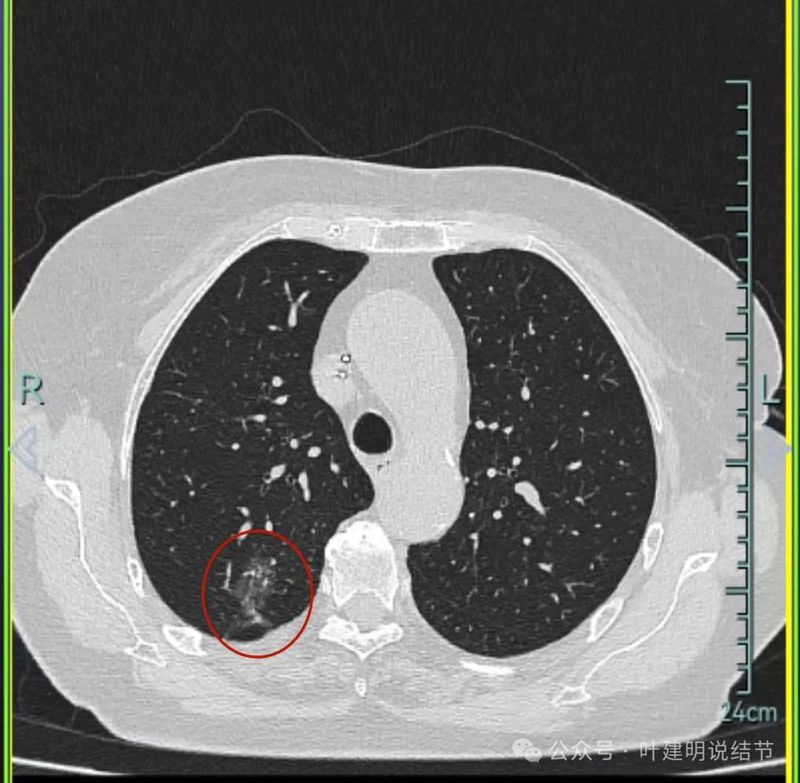

先来看2023年1月时的影像:

右上叶混合密度病灶,有毛刺征,轮廓较清,单次单处看是要考虑恶性的;左上叶磨玻璃结节,轮廓较清,密度较淡,瘤肺边界部分边缘稍不清。

右上叶混合密度结节,有分叶征,内部密度杂乱,有毛刺征,灶内有空泡征,单处单灶看也是与恶性较为符合;左上叶两处磨玻璃阴影,轮廓稍糊,边界稍不清,感染稍倾向炎性些。

右下混合密度结节,有明显血管进入,轮廓较清,瘤肺边界较清,单灶单处看也像恶性些;

左下胸膜下混合密度结节,边缘不平有毛刺,但毛刺不是很锐利,与胸膜侧紧贴,没有明显牵拉。

右中叶混合密度结节,有血管进入,表面不平,略有胸膜牵拉,但感觉病灶显散,聚拢性不够。

右下叶磨玻璃结节,贴着叶间裂,缺乏收缩力,中间有小空泡,单灶单看恶性不能除外,但略倾向炎性点。

右中叶磨玻璃病灶,轮廓稍糊,瘤肺边界欠清,呈片状,与炎性更符合点。

当时影像考虑:

从上述两肺多发病灶来看,虽有多处也恶性的混合密度结节也是符合的,但由于病灶太多,有的轮廓与边界模糊,首次发现肯定要先考虑感染性病变,并依病毒感染予以治疗并适时复查。因为退一步讲,即使多原发肺癌是这个样子,近80岁的高龄,也肯定不能先考虑手术来解决,那是切不光的。